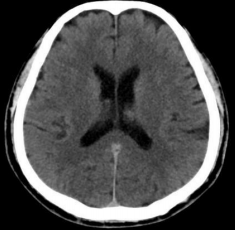

注:图 3 4 均为头颅 CT 平扫检查结果图片,图 3 为脑出血患者头颅 CT 扫描显像,红色箭头处表示该处有高密度出血, 周围脑组织水肿,中线结构向右侧移位;图 2 为正常颅脑 CT 扫描显像,双侧脑组织对称,灰白质对比清楚,中线结构居中。